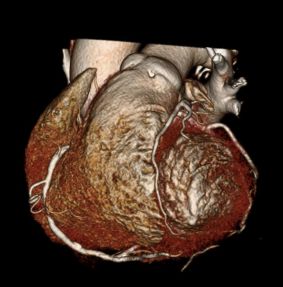

Heart CT is a fast screening exam done without contrast on a 16-slice CT scanner at RAYUS centers throughout Puget Sound. The scan allows us to non-invasively look at the three major coronary arteries that carry blood to your heart muscle.

With Heart CT, we can detect and measure the size and density of calcified plaque, presenting that as a quantitative score. The higher the calcium score the greater the amount of underlying CAD and the greater the risk of a subsequent cardiac event.

Severe Calcification